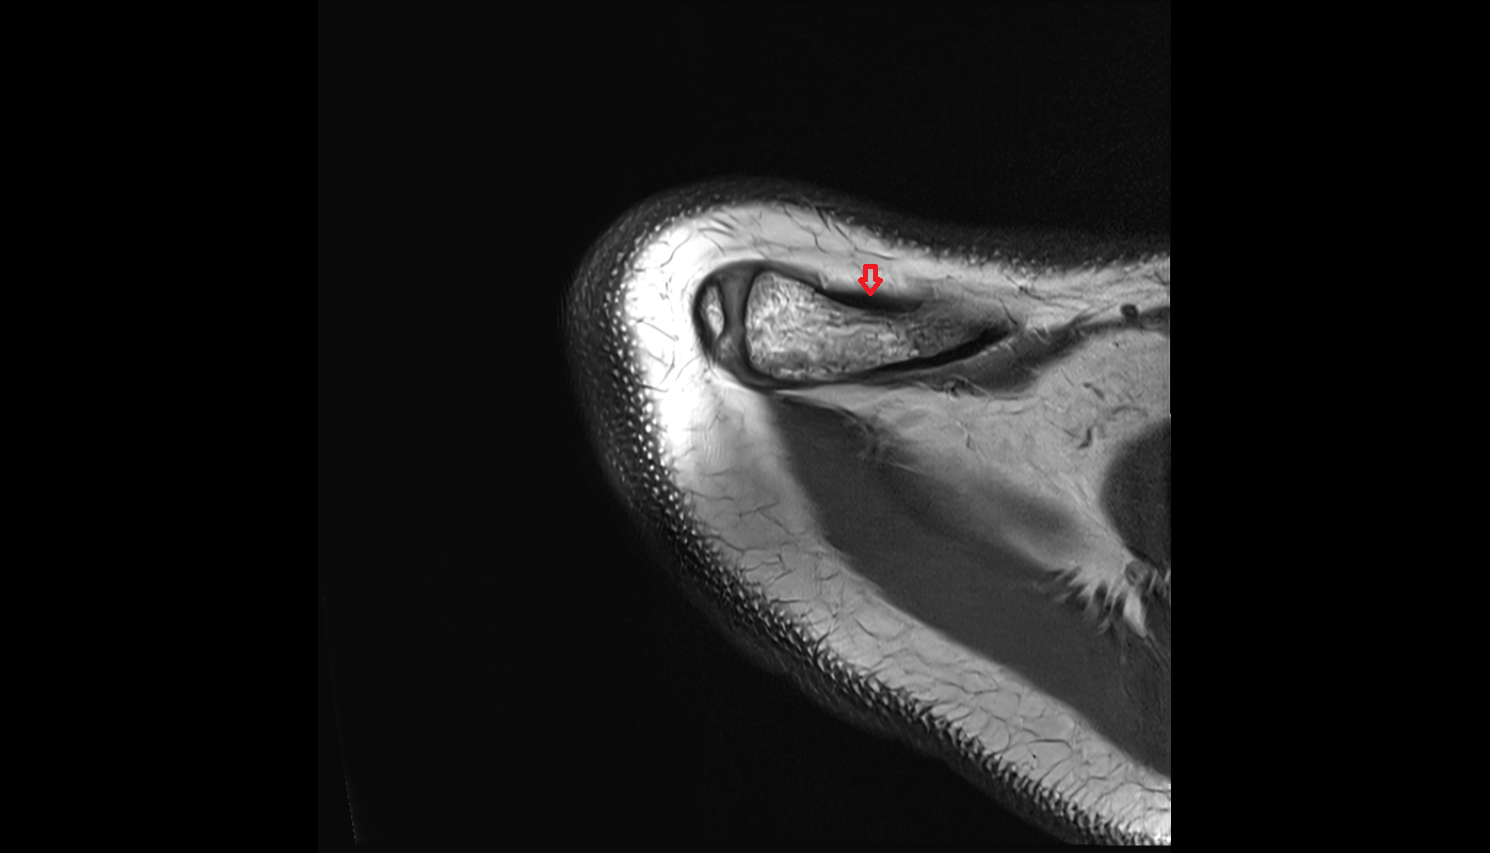

- Temporomandibular joint

- Articular disc of temporomandibular joint

- Anterior Band of Articular Disc TMJ

- Posterior band of articular disc, TMJ

- Intermediate zone of articular disc

- Articular eminence

- Articular surface of mandibular fossa

- Articular tubercle